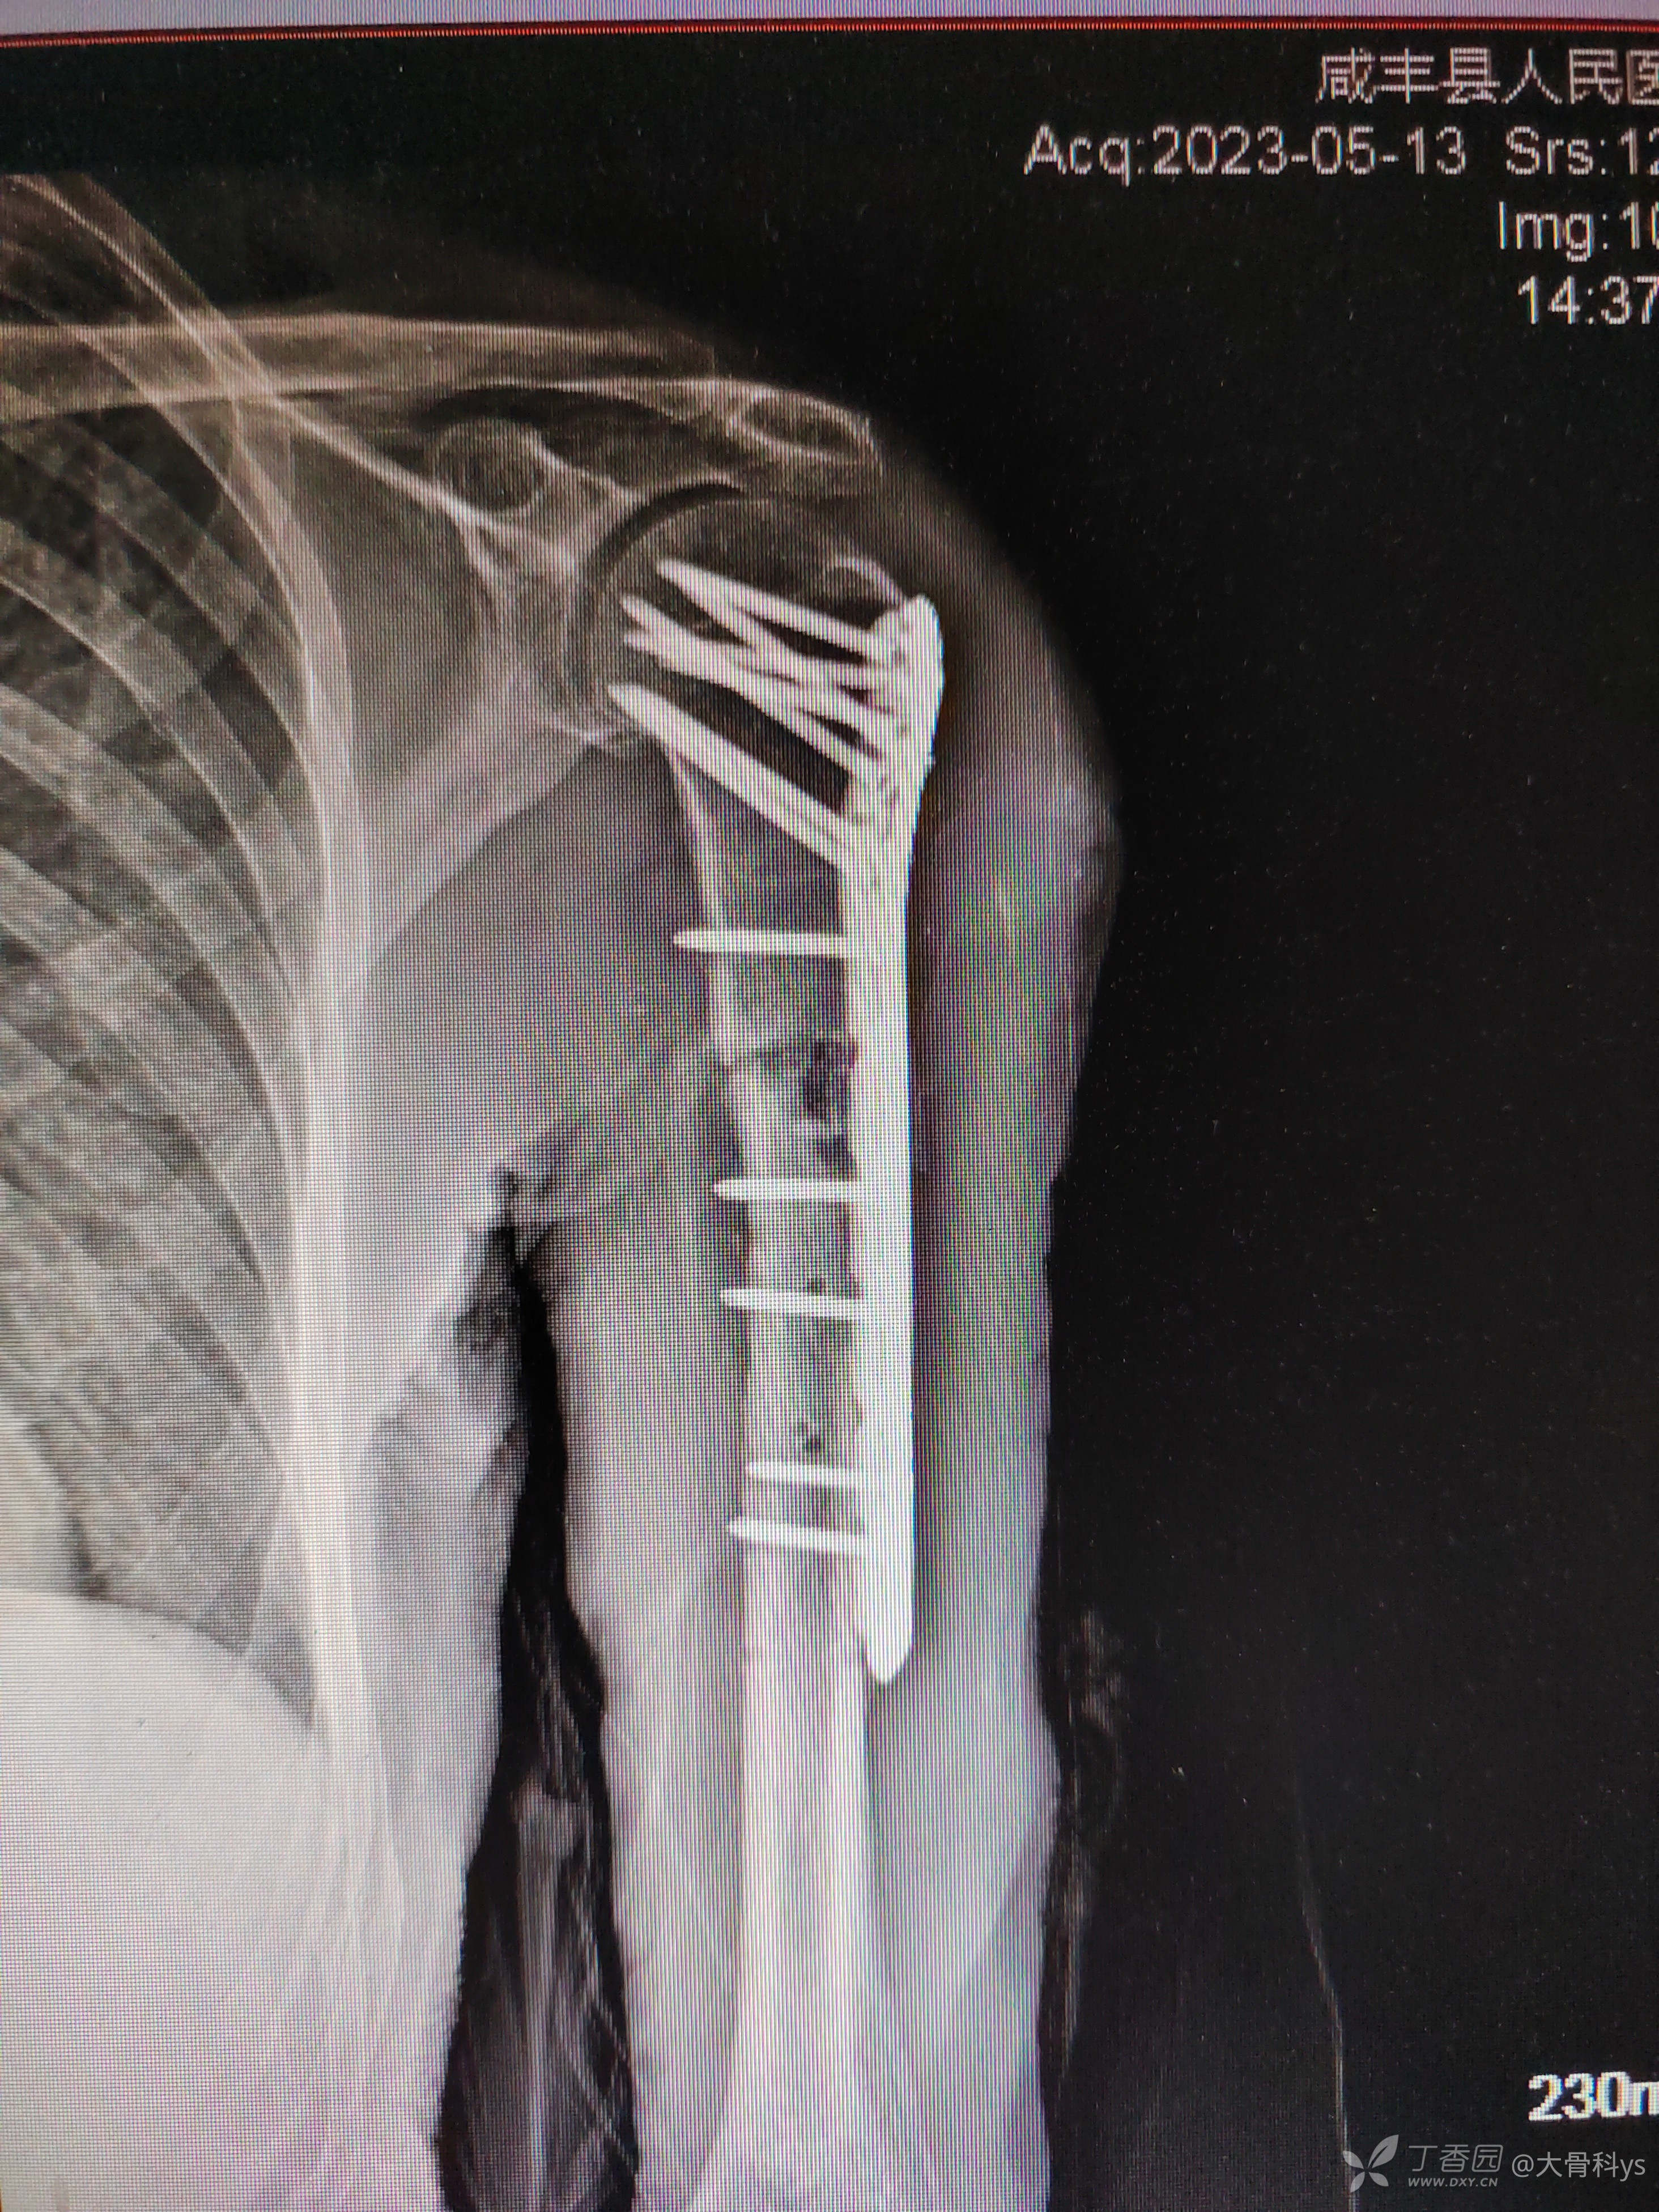

近期复查照片

患者主诉无再次外伤,患肢疼痛已数月,但术后一直未复查。本次入院后再次手术治疗,术中发现有断钉,骨断端骨不连、纤维连接。术中骨断端清理、加压固定,取自体髂骨植骨。术后照片